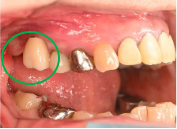

Before

※赤丸は、歯根が破折していたため抜歯しました

※黄色丸は、2006年10月に埋入したインプラント

After

※緑丸は、今回埋入したインプラント